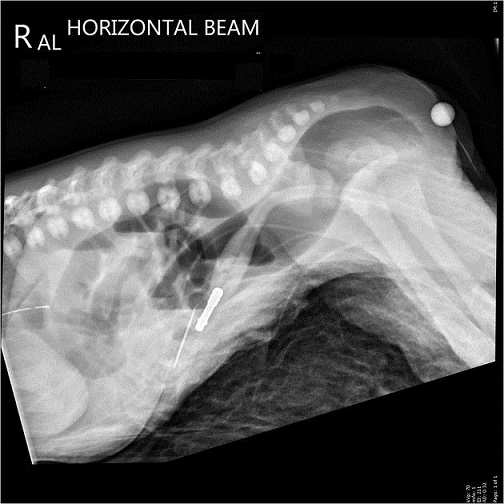

Invertogram d'une

imperforation anus . Image de receuillir a position

inverse on peut en verifie la distance entre

image de distendue gazeuse du cul de sac du colon

avec orifice externe de l'anus ( repair metalique )

. |

imperforation anal en position decubitus " priera

Mahometa " , Rayon X central est place horizontal

parallelique avec le plan de la table |

Il y a deux forme ( type ) de

imperforation anale :

- Forme haute ( 55%) : si la distance

entre le cul de sac inferieure du colon et

orifice externe de l'anus est de plus > de 2cm

et cette forme est souvent presenter en associe

avec les autres malformations :

urogenitale , rachidienne et cardiacque

- Forme basse ( 45%) : se verifie par la

distance entre cul de sac du colon et orifice

externe de l'anus est inferieuse de < 2cm de

distance . Cette forme avait de bon prognostic

de normalisation du transit

Cliche face d'une

imperforation d'anus |